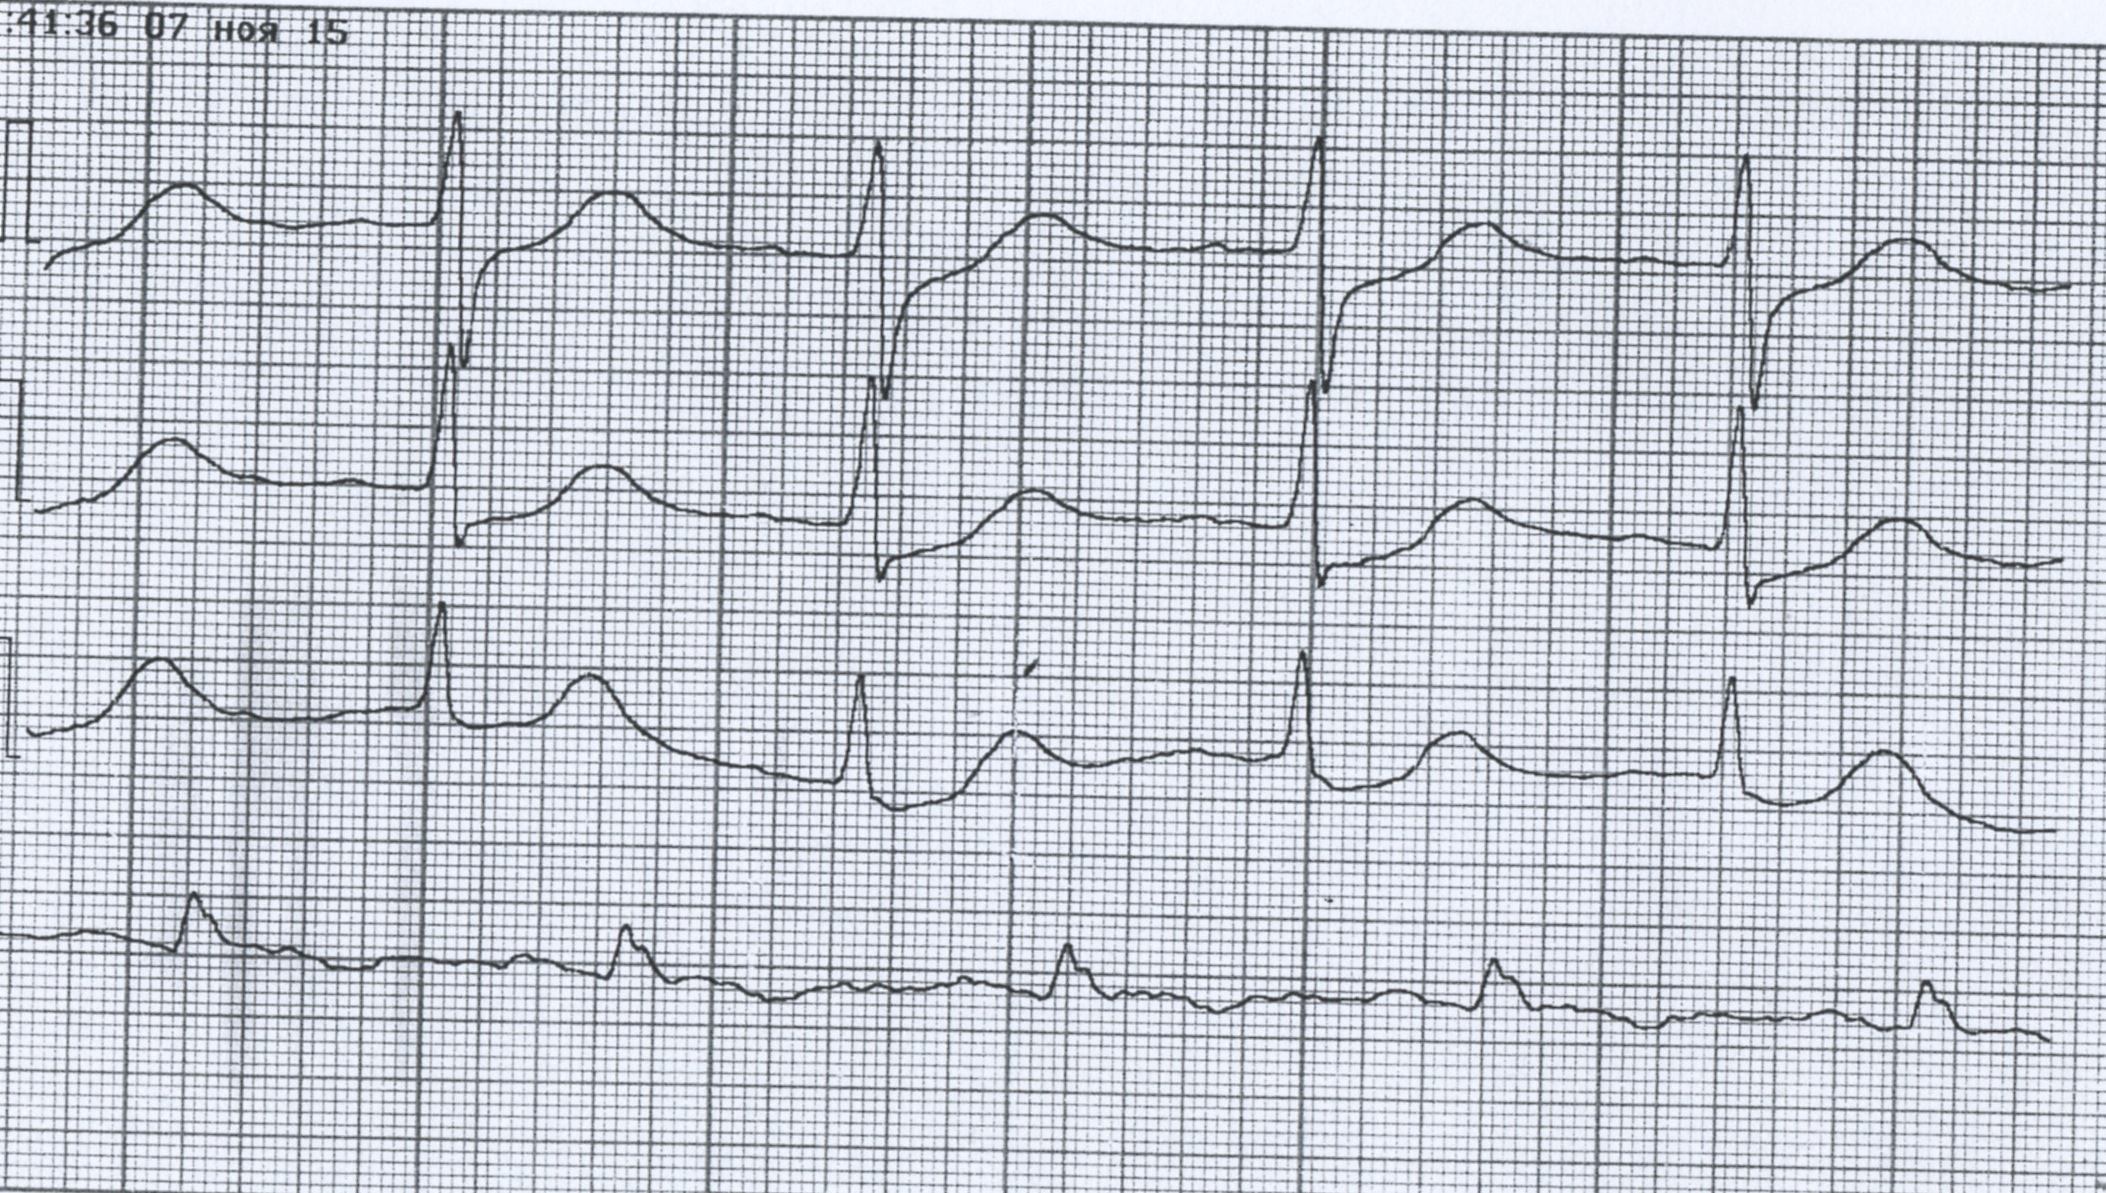

Желудочковая тахикардия. Улетевшая тема 6953.

1 (1).jpg

1 (1).jpg [ 58.86 KiB | Просмотров: 69519 ]